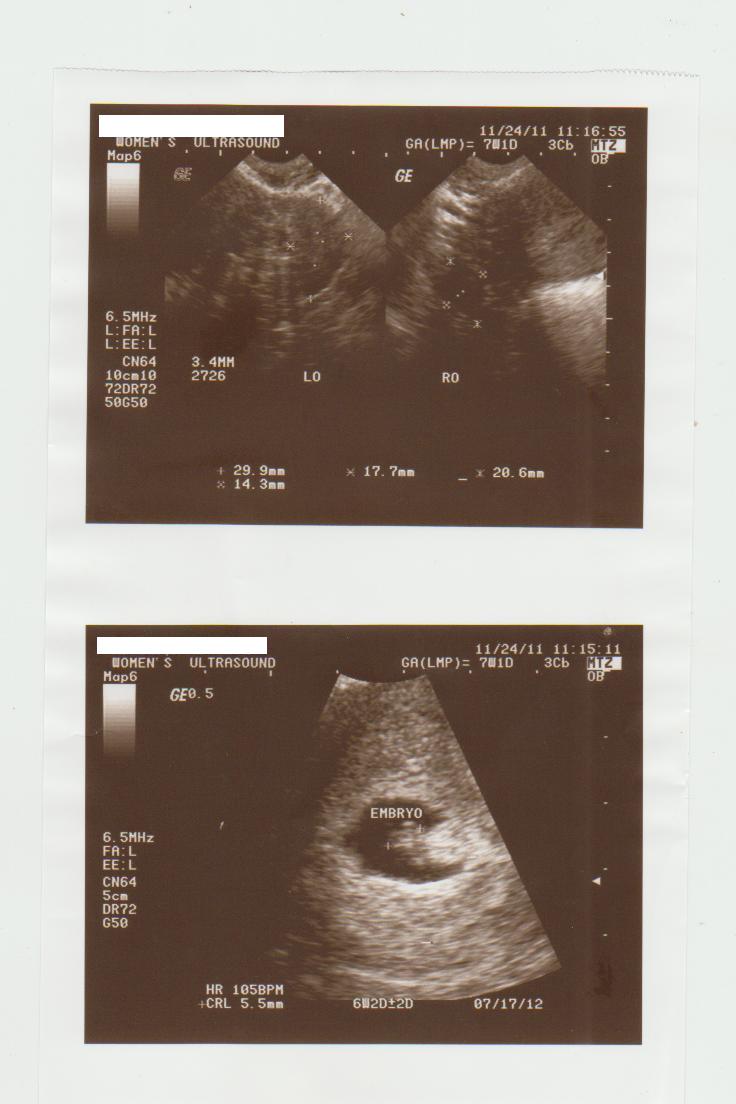

October 17, 2011 - Its my Day 13 , I had my first Follicle Monitoring and I had a dominant follicle

size 1.5x1.2cm on my left ovary on this 4th cycle and I went to my OB alone DH and I are still not

good terms. My Ob said i need to have repeat FM on my Day15, and she plan to give me a shot of

pregnyl if my follicle gets bigger atleast 1.8cm. I went home and inform DH about it but sad to say

no reaction and no Baby Dance till now. I see my self talking to my tummy telling please follicle to

not burst yet.

October 20, 2011 - I had my FM again and size is 2.1 x1.7cm already. When we went to my OB she ask

i had my another FM in the morning, my hubby said just spend the money we save for

Pregynl Shot to take the Fm again. Although i told him i just had my Fm yesterday most

probably it still the same size but he insist. So I did and im not wrong same size 2.14 x

1.44cm We didn't do any baby dance anymore since the last and first one on this cycle.